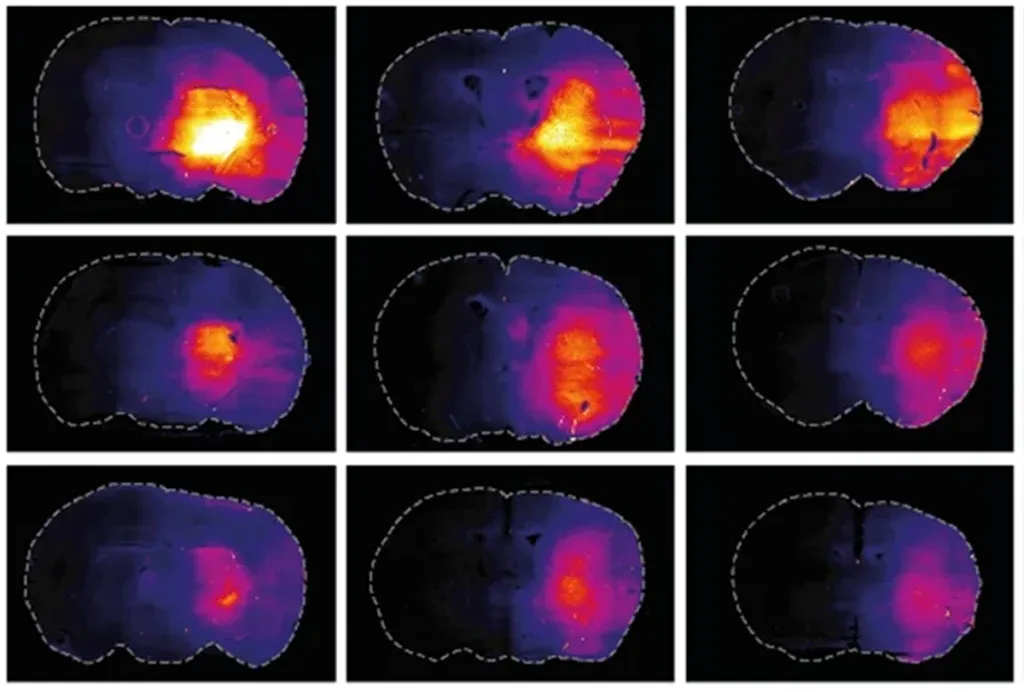

The glymphatic system is a specialized clearance network in the brain, first described in 2012. It uses cerebrospinal fluid (CSF) to flush metabolic waste out of brain tissue and move it toward elimination pathways.

When you’re awake, brain cells are packed tightly together to allow fast communication. During deep sleep, those cells shrink slightly, creating space between them. That space allows cerebrospinal fluid to move through brain tissue and wash waste out efficiently.